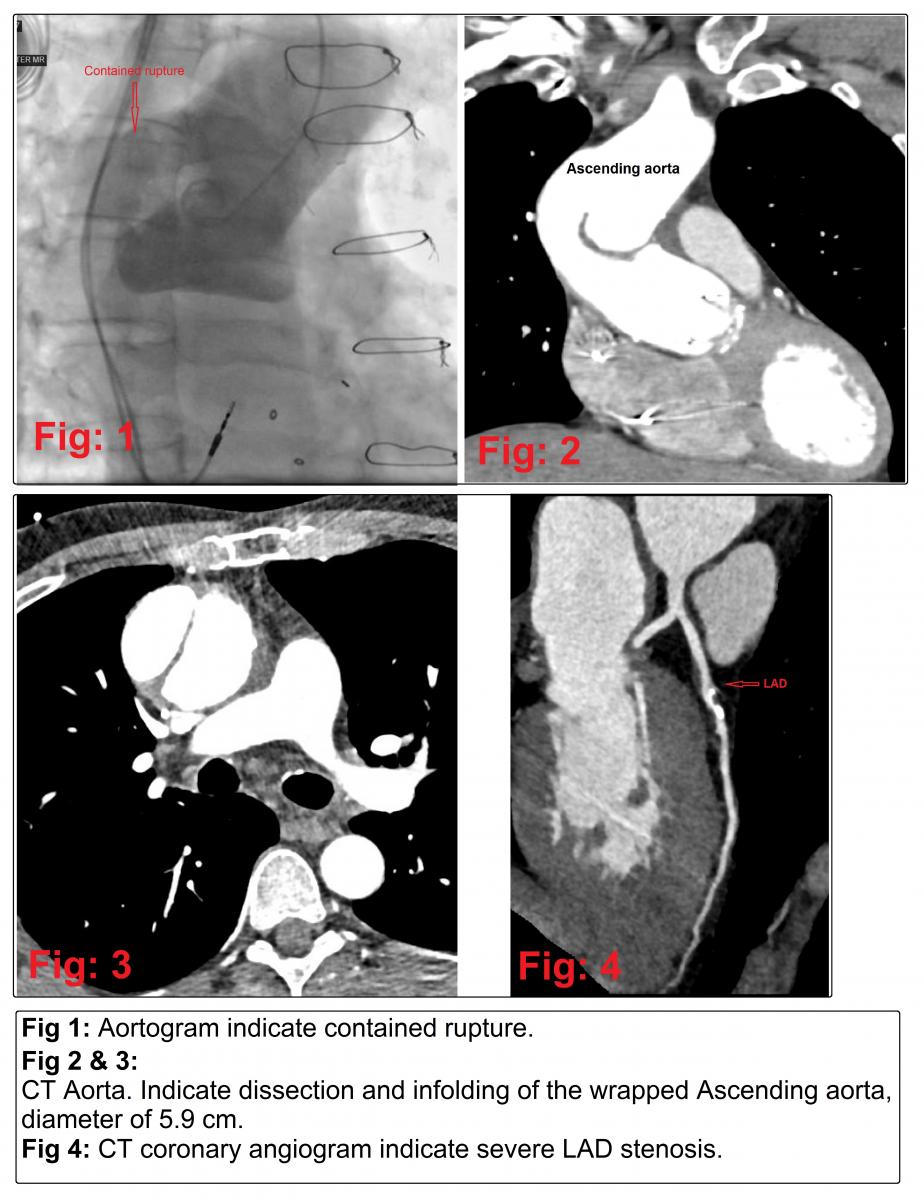

- Aortogram (Figure 1): indicate contained rupture.

- CT aorta (Figure 2): Dissection and infolding of the wrapped Ascending aorta. Proximal aortic arch measures about 42mm and mid arch 30 mm.

- CT aorta (Figure 3): Ascending aorta measures about 59mm at the level of the right pulmonary artery.

- CT-coronary angiogram (Figure 4): mid LAD plaques with severe stenosis. CT FFR was < 0.50 in the LAD beyond the stenosis. Other coronary arteries were normal.